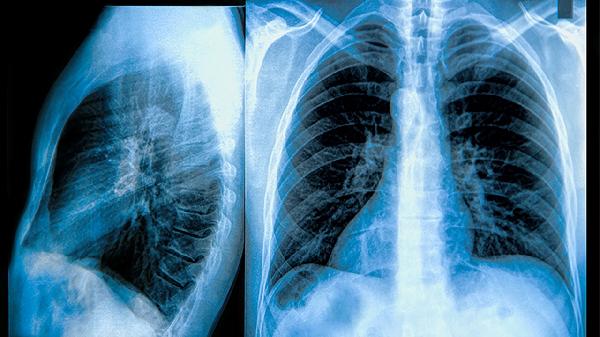

慢阻肺患者可遵医嘱使用布地奈德福莫特罗粉吸入剂、沙美特罗替卡松粉吸入剂、噻托溴铵粉吸入剂、氨茶碱片、乙酰半胱氨酸颗粒等药物。慢阻肺是一种以持续气流受限为特征的慢性气道炎症性疾病,需长期规范用药控制症状并减少急性加重风险。